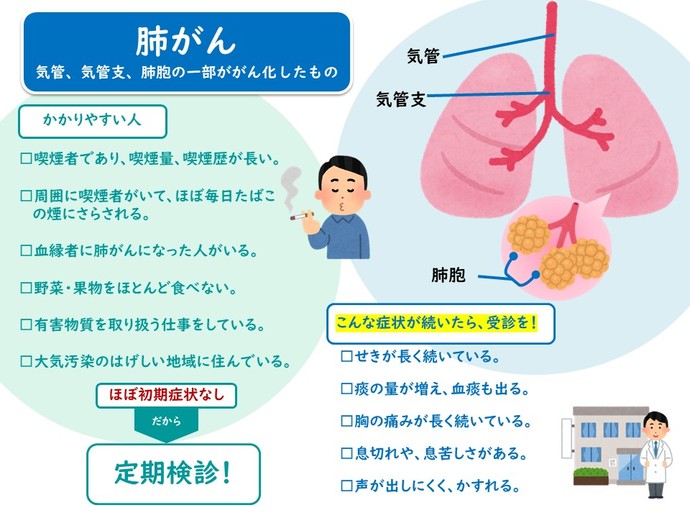

以下の場合、がんのリスクが高まります。

- 結節が大きい

- 小結節は葉状または尖った表面を持っているように見えます

- あなたは現在または元喫煙者です

- 肺がんの家族歴がある

- あなたはアスベストにさらされています

- 慢性閉塞性肺疾患(COPD)の病歴がある

- あなたは60歳以上です

肺の斑点ががん性である場合、特定の種類のがんに関連した症状が現れることがあります。たとえば、肺がんによって引き起こされる増殖は、持続的な咳や呼吸困難を引き起こす可能性があります。